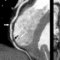

Acute aortic dissection is a potentially catastrophic emergency associated with high mortality. CT is a first-line diagnostic modality for the diagnosis. In a recent review that evaluated the accuracy of MDCT in acute aortic dissection, the authors reported a sensitivity of 99% and a specificity of 100% and concluded that CT is the test of choice, given its speed and cost-effectiveness. 23 The visualization of a dissection flap, of the true and false lumen, and of the origin and distal extent of the dissection are well characterized by CT (Figures 5 and 6). 24